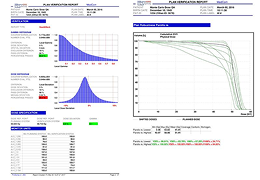

分析智能。

这些功能利用数字控制面板分析运营、业务和临床绩效。

使管理员能够跟踪关键参数,包括平均曝光率、拒绝的影像和探测器统计信息。

帮助确定需要改进的方面,支持为员工和部门制定适当的改进计划。